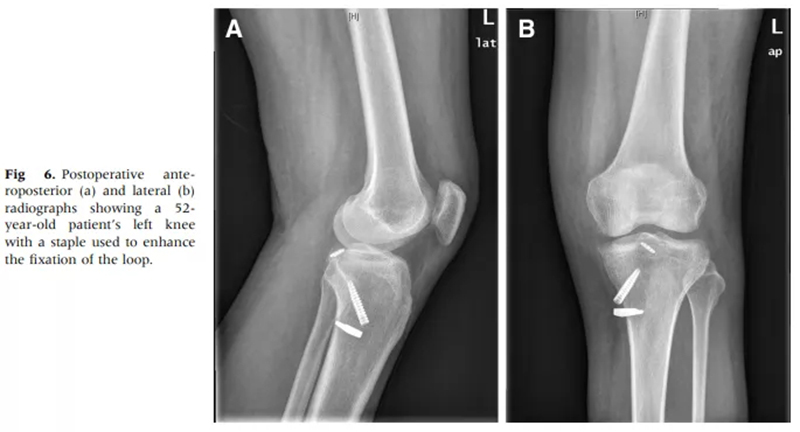

徐醫(yī)附院通過關(guān)節(jié)鏡微創(chuàng)手術(shù),只需做4個8mm左右的小切口,通過做一個直徑0.45cm、長約5cm的骨隧道,將長線環(huán)帶袢鈦板引入關(guān)節(jié)內(nèi),鈦板固定骨折,即可取得很好的穩(wěn)定性,經(jīng)過長時間大規(guī)模的病例累計,形成了40例的總結(jié)分析和評估,系統(tǒng)地講述了關(guān)節(jié)鏡下微創(chuàng)處理后交叉韌帶撕裂的手術(shù)方式、要點和治療效果,對行業(yè)發(fā)展也具有很好的借鑒意義。

骨折固定更穩(wěn)定,便于術(shù)后及早進(jìn)行功能鍛煉。